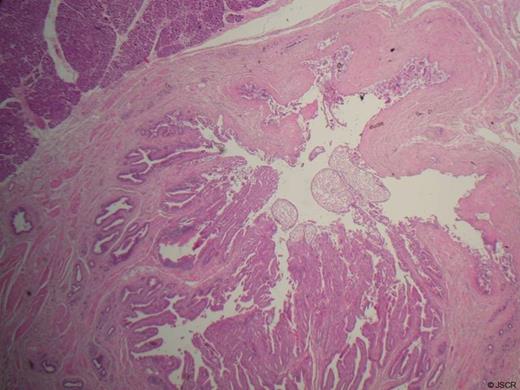

The histology of the operative specimen revealed cholesterol polyps in the distal CBD associated with a juxta-papillary duodenal diverticulum (Figure 2).

Histology at x20 magnification demonstrating cholesterol polyps at the convergence of the distal CBD and main pancreatic duct.